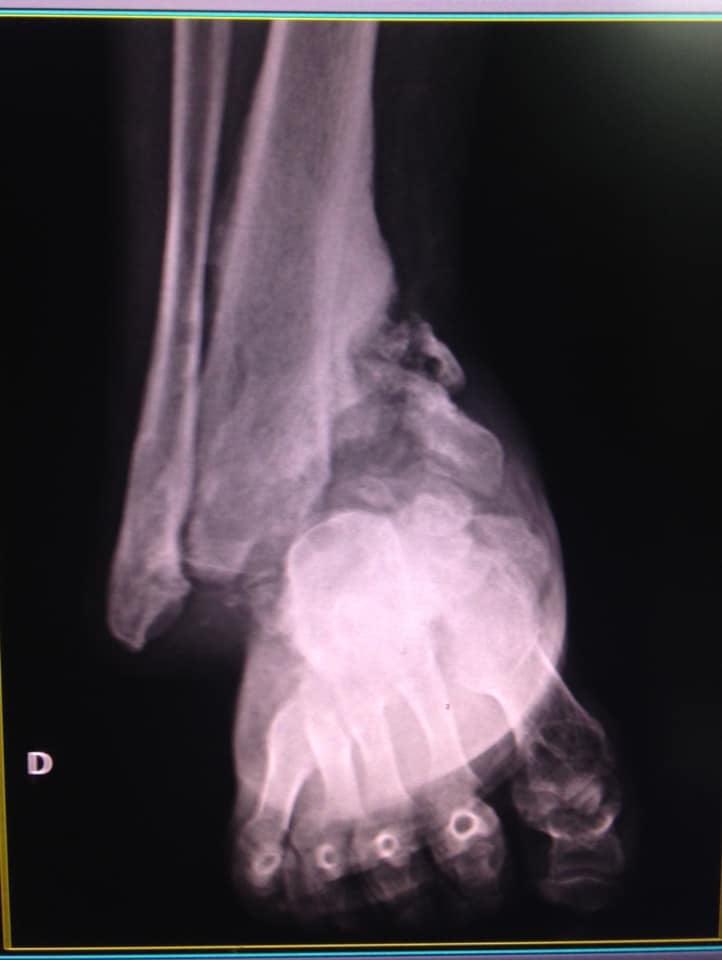

‘’Eu com 35 anos de idade tenho que aceitar ficar sem andar porque o país em que vivo não cobre a cirurgia? Aceito que não vou mais andar?’’, questionou a paciente. Ela apresentou várias radiografias e diz que os pés ‘’desabaram’’ por conta da doença rara.

‘’…não precisa ser médico, tão pouco especialista para ver as fraturas, elas são enormes e gravíssimas e se vê a olho nu’’, lamentou mais uma vez.